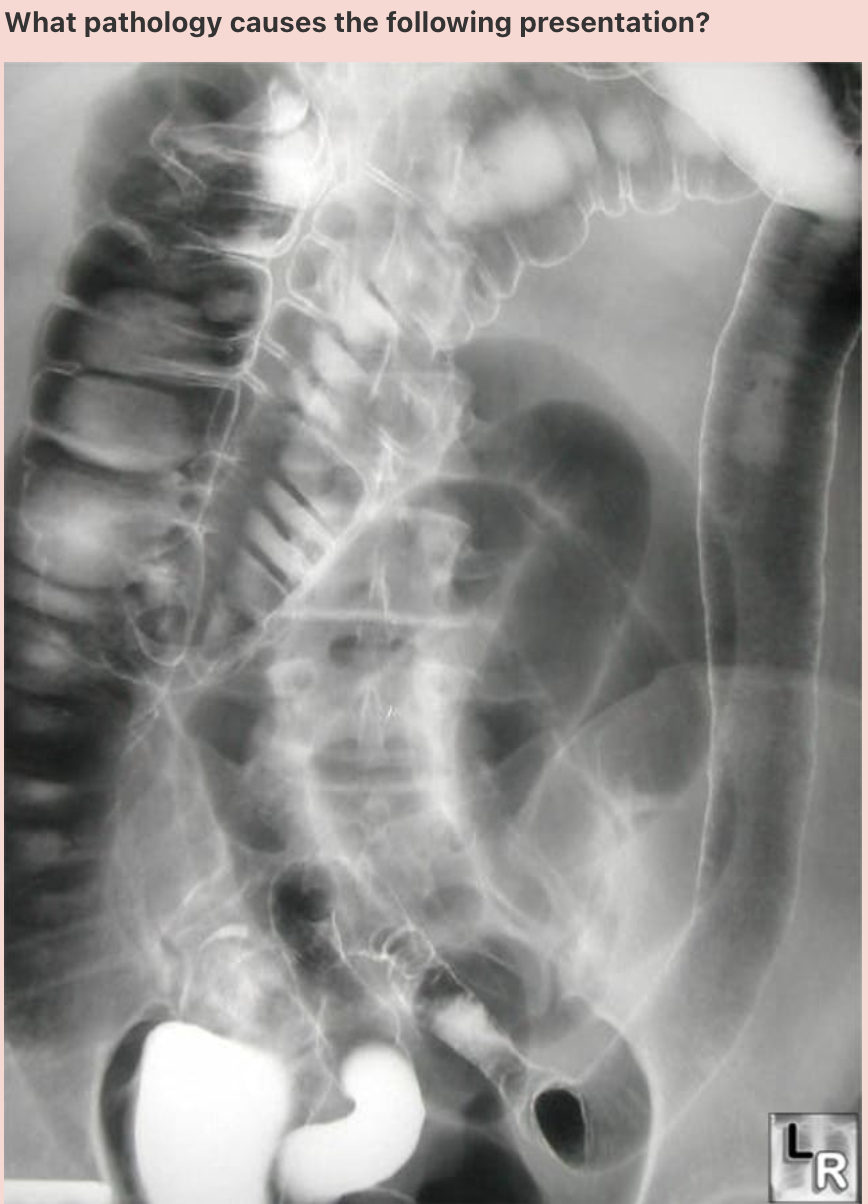

What pathology causes the following presentation (shown by the white arrow)?

Answer: Crohn’s disease

Explanation: Known as ‘string sign’, this observation is classically found in Crohn’s disease. It occurs in both stenotic and non-stenotic phases of the disease; in non-stenotic regions, it is of variable width and is secondary to oedema and GI spasm. In stenotic regions, the diameter is fixed secondary to the scarring and fibrosis seen in severe Crohn’s disease presentations.